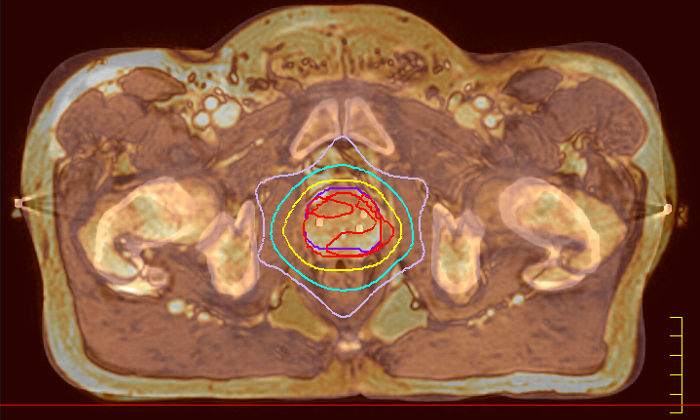

With its exceptional soft-tissue visualization capabilities and wide range of image contrasts, MRI has become a powerful tool to help more precisely define tumor boundaries. This is particularly important as it has been established that there is a high degree of uncertainty in target volume delineation, and it is even reported to represent the largest uncertainty in the entire radiotherapy process for most tumor sites**. Better visualization of the target area and nearby organs-at-risk is a key factor in enhancing target volume delineation. MRI’s expanding role also can be attributed to its functional imaging capabilities, which can inform both target characterization and treatment response.

With its superior soft tissue contrast compared to CT, MRI offers exquisite visualization of tumor boundaries and proximity to nearby critical structures.

The ability to tune contrasts can provide even more valuable information about tumor characteristics and tumor extent to facilitate enhanced delineation, and also provides possibilities for dose boosting strategies.